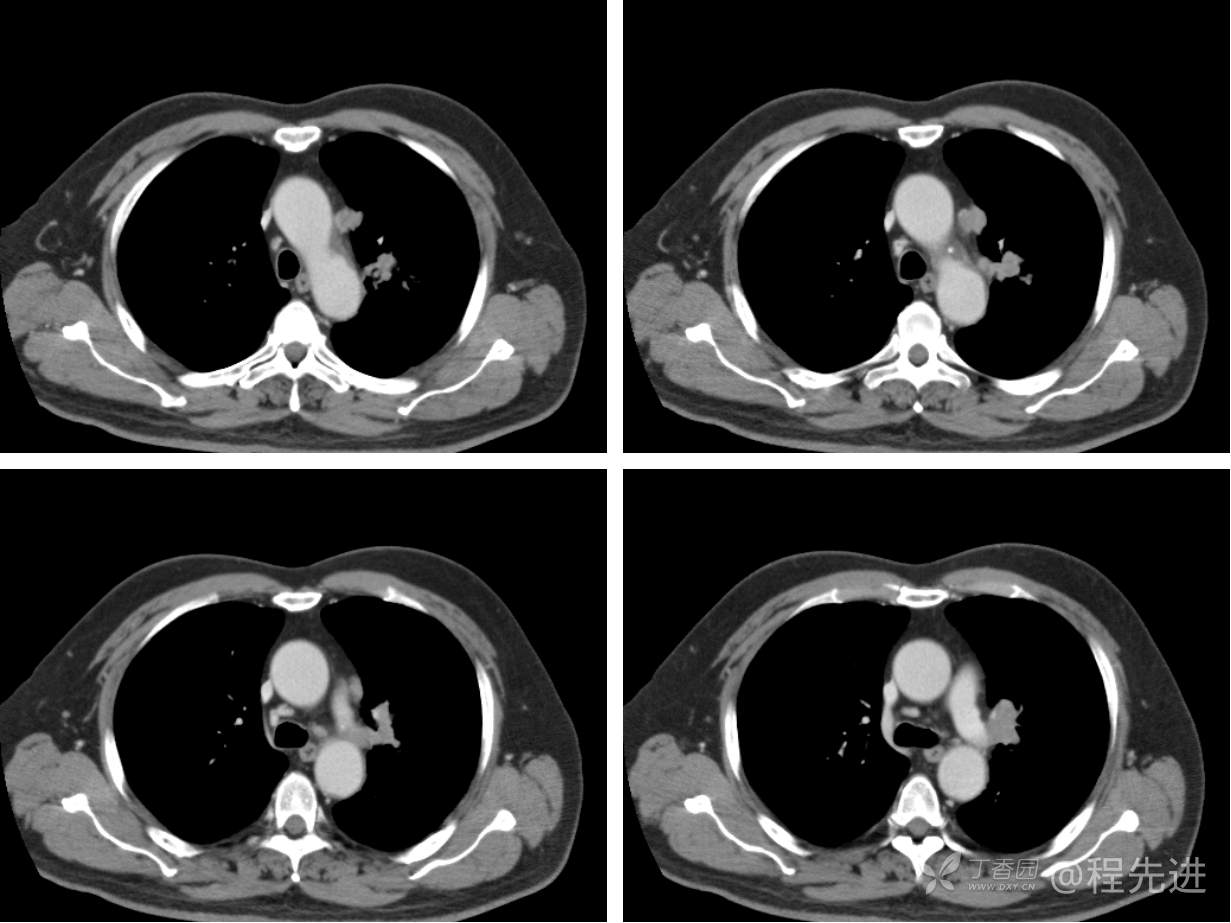

现病史概要:患者入院前约半月无明显诱因下出现咳嗽、胸闷症状,无明显发热症状,咳少量白痰,无明显咯血、喘息、头晕等不适,就诊我院查胸部CT示上纵膈肿物,左肺上叶支气管内肿物,现为行进一步治疗收入胸外科,患者近来饮食睡眠尚可,二便如常。